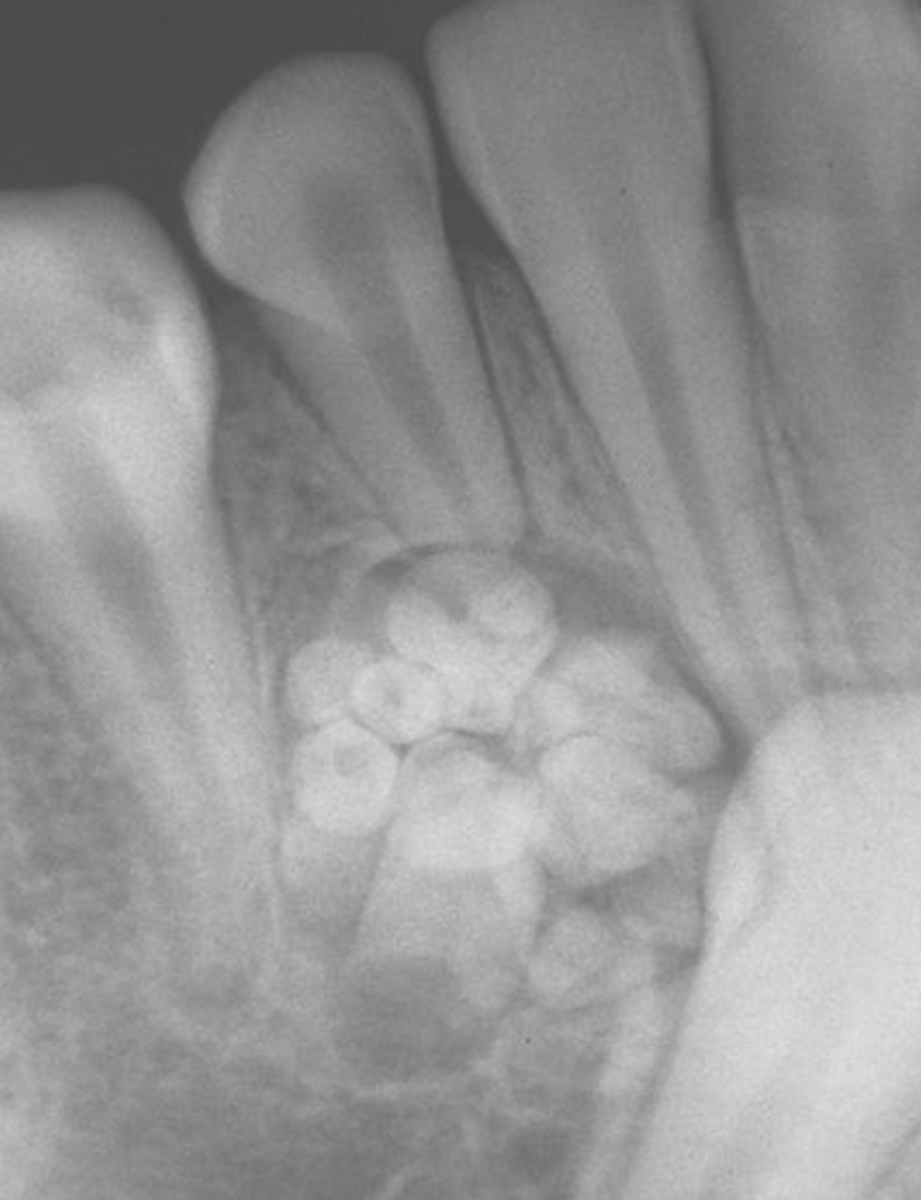

Radiographic Signs of Odontoma

mixed

target lesion